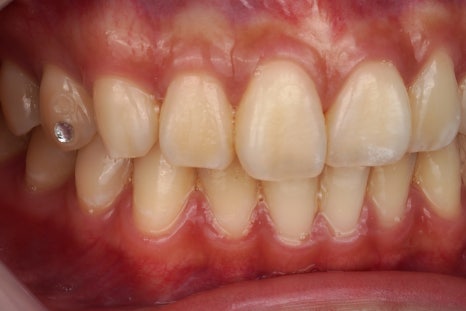

제거 전

제거 후

진짜 깨끗하게 떨어졌죠

그냥 뗀 게 아니라

치과용 기구를 이용해서 정확히 떼어내고

전문적인 앞니 치료 도구들을 활용해서

치아 표면을 활택하게 만듭니다.

어디에 접착제가 묻어있었고

어디에 투스젬이 있었는지

정말 감쪽같이 떨어지지 않았나요?